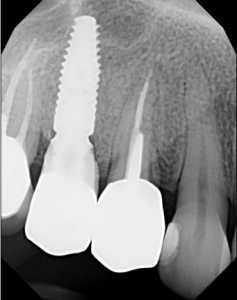

This video demonstrates a fully guided immediate implant placement protocol following premolar extraction, combined with immediate provisional restoration. The case highlights a digitally driven workflow designed to enhance accuracy, efficiency, and prosthetically guided implant positioning.

Step-by-step, the procedure covers atraumatic tooth extraction, guided implant placement using a surgical guide, and chairside fabrication and delivery of an immediate provisional restoration. Clinical considerations for achieving primary stability, soft tissue preservation, and optimal emergence profile are emphasized to support predictable esthetic and functional outcomes.